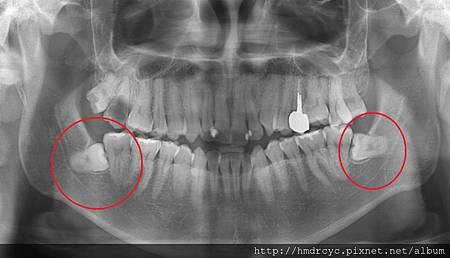

許多智齒根本長不出來

就是俗稱的水平智齒

如果智齒完全被包覆在骨頭裡面就算了

這樣發炎的機會也小

不想拔可以先觀察

沒問題就不理它

但大部分的智齒不會這麼理想

往往不是只露出一點點

就是沒有完全露出